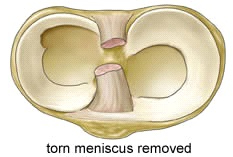

Meniscus letsels

Kunnen ontstaan door een ongeval (posttraumatisch) of door slijtage (degeneratief)

Gezien de functie van de meniscus (optimalisatie van de gewichtsverdeling tussen het boven en het onderbeen) is het impact van deze letsels ( zeker bij jonge patiënten) niet te onderschatten daar deze letsels kunnen leiden tot vervroegde slijtage van het kraakbeen (artrose)

De behandeling van dergelijke letsels is, afhankelijk ook van het type letsel en de leeftijd van patiënt, zo behoudend (conservatief) mogelijk en kan bestaan uit een arthroscopische(via kijkoperatie)

meniscushechting

Zo beperkt mogelijke (partiële) meniscus resectie.

Meniscus transplantatie in specifieke gevallen.